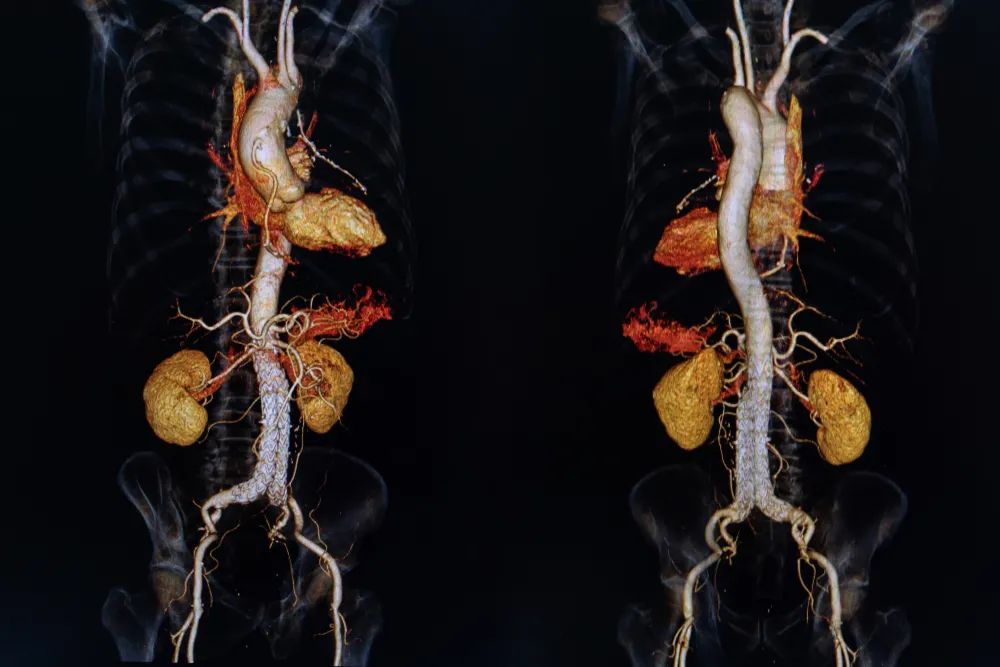

CT 的好处在于避免了层叠图像的干扰,图像更加清晰且分辨率高。它还可以合成一个三维立体图像,相当于给你的身体建个模,对于疾病诊断和手术规划可太重要了。

图片来源:站酷海洛

CT 即便如此强大,但依然有它的局限性,对于一些密度十分接近的软组织如脑、脊髓、肿瘤病灶,依然无法提供足够清晰的图像。